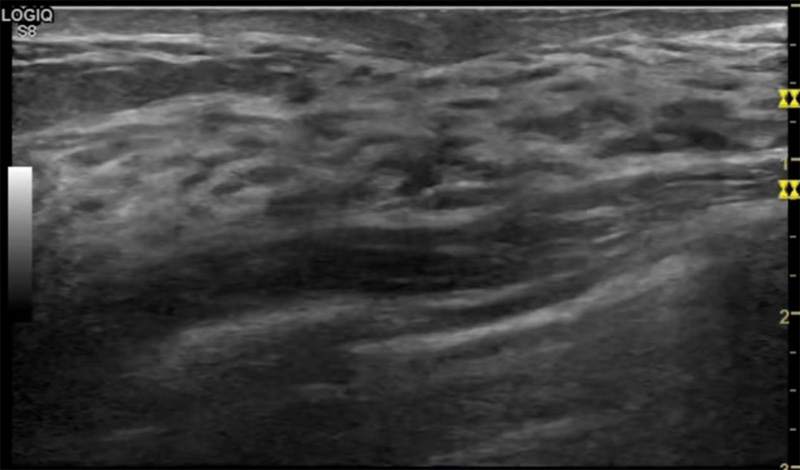

乳房脹痛,觸摸疼痛,手摸起來(lái)感覺(jué)有腫塊。這個(gè)是什么問(wèn)題呢?醫(yī)生診斷一般是乳腺增生。那么在乳腺超聲設(shè)備檢查后,報(bào)告單卻顯示雙乳未見(jiàn)明顯占位性病變。乳腺增生是很多女性,特別是育齡期女性都有的經(jīng)歷、到底乳腺增生癥狀有哪些?會(huì)給我們帶來(lái)怎樣的影響呢?乳腺增生不是腫瘤跟炎癥。乳腺組織增生及退行性變跟內(nèi)分泌功能紊亂有關(guān)系。正常的生理改變。還有乳腺病,良性乳腺結(jié)構(gòu)不良等名稱(chēng)。

乳腺增生有什么癥狀,病因?比較典型的就是乳房疼痛,特別是經(jīng)前癥狀比較重,經(jīng)后就有所緩解。有時(shí)候還能碰到乳房硬塊。根據(jù)經(jīng)期的變化而變化硬度大小都有變。乳腺在內(nèi)分泌激素,伴隨月經(jīng)周期有增生問(wèn)題。內(nèi)分泌激素代謝失衡,雌激素水平增高,出現(xiàn)乳腺組織增生過(guò)度,增生組織不退的情況下,就會(huì)有乳腺增生癥狀。這個(gè)不會(huì)增加乳腺癌的風(fēng)險(xiǎn)。所以不用緊張的。不過(guò)乳腺癌的病人都會(huì)有乳腺增生。所以乳腺增長(zhǎng)有沒(méi)癥狀,都需要進(jìn)行常規(guī)的體檢。